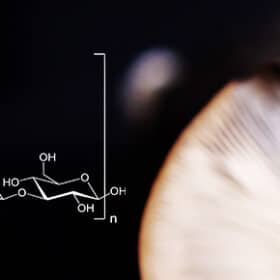

Lentinane: Origine, Description & Bienfaits Of fascinating leur pair trained à tentomposer les matières organiques...

Érinacines: Approhes et Perspectives Dans the neuroprotection Them Érinacines Sont des Bioactifs compositions Dérivés du Champignon Hericium Erinaceus, Également Connu...